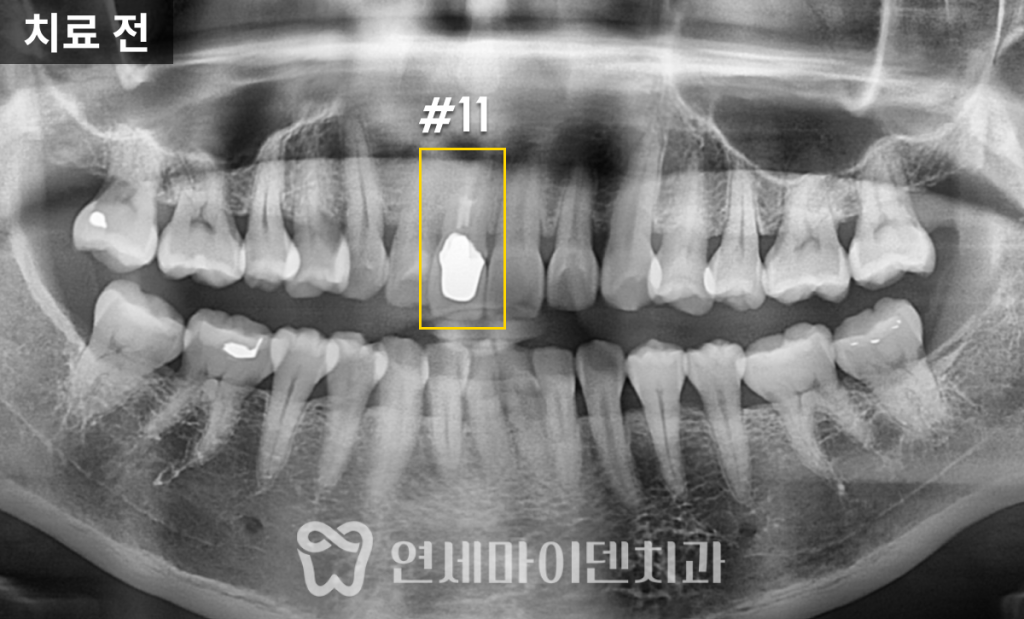

초기 검사에서 신경치료가 제대로 이루어지지 않은 흔적이 보였습니다.

신경관 내부를 꽉 채워야 하는 신경치료 재료가 빈틈이 많아서

감염이 쉽게 발생할 수 있는 환경이었고,이는 신경치료 실패의 주요 원인 중 하나였습니다.

또한, 치근단 절제술도 진행하긴 했지만,

뿌리 끝 염증을 제거하는 과정이 충분하지 않았던 점도 확인되었습니다.📌 검진 결과 요약

1️⃣ 기존 신경치료에서 신경관 충전이 완벽하지 않음 (빈틈이 많음)

2️⃣ 치근단 절제술을 했지만 염증 부위가 완전히 제거되지 않음

3️⃣ 내부에 금속 기둥(포스트)이 삽입되어 있음앞니 재신경치료 과정